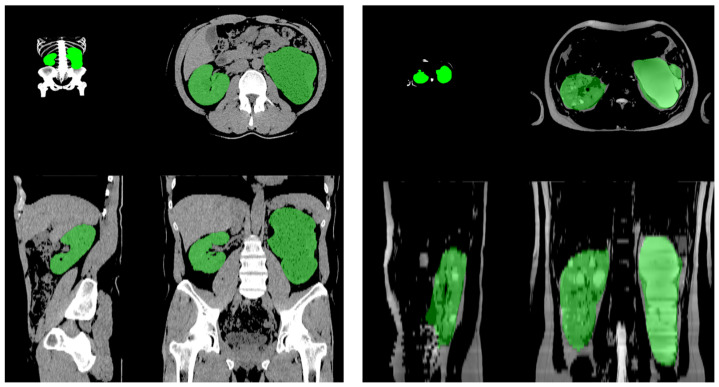

背景:多囊肾病(PKD)的Mayo影像分类(MIC)是临床治疗决策的重要依据;然而,对其评价的体积评估仍然是繁琐和不准确的。虽然测量PKD患者总肾体积(TKV)的椭球方法使用计算机断层扫描(CT)提供了实用的TKV估计,但其不一致性和不准确性是局限性,强调需要在现实世界的诊所中改进,易于使用的技术。方法:采用基于卷积神经网络的分割模型(3D Dynamic U-Net)对某三级医院32例PKD患者的TKV进行测量,比较人工椭球法和人工智能(AI)肾脏体积法。结果:中位年龄为56岁,平均TKV为1200.24 mL。大多数患者采用椭球法,类似于AI容积法,被分配到Mayo Clinic的1B和1C分类。AI容积法优于椭球法,评分高度相关(AI vs.肾脏病学教授ICC: r = 0.991, 95%可信区间(CI) = 0.9780 ~ 0.9948, p < 0.01;AI vs.训练有素的临床医生ICC: r = 0.983, 95% CI = 0.9608 ~ 0.9907, p < 0.01)。Bland-Altman图还显示,教授和AI容积法的平均差异无统计学意义(平均差异为159.5 mL, 95% CI = 11.8368-330.7817, p = 0.07)。结论:基于人工智能的肾脏体积测量与专家手动测量结果非常一致,为临床实践中的TKV评估提供了可靠、高效的替代方法。这对治疗PKD和优化治疗结果是有帮助和必要的。

Background: The Mayo imaging classification (MIC) for polycystic kidney disease (PKD) is a crucial basis for clinical treatment decisions; however, the volumetric assessment for its evaluation remains tedious and inaccurate. While the ellipsoid method for measuring the total kidney volume (TKV) in patients with PKD provides a practical TKV estimation using computed tomography (CT), its inconsistency and inaccuracy are limitations, highlighting the need for improved, accessible techniques in real-world clinics. Methods: We compared manual ellipsoid and artificial intelligence (AI)-based kidney volumetry methods using a convolutional neural network-based segmentation model (3D Dynamic U-Net) for measuring the TKV by assessing 32 patients with PKD in a single tertiary hospital. Results: The median age and average TKV were 56 years and 1200.24 mL, respectively. Most of the patients were allocated to Mayo Clinic classifications 1B and 1C using the ellipsoid method, similar to the AI volumetry classification. AI volumetry outperformed the ellipsoid method with highly correlated scores (AI vs. nephrology professor ICC: r = 0.991, 95% confidence interval (CI) = 0.9780-0.9948, p < 0.01; AI vs. trained clinician ICC: r = 0.983, 95% CI = 0.9608-0.9907, p < 0.01). The Bland-Altman plot also showed that the mean differences between professor and AI volumetry were statistically insignificant (mean difference 159.5 mL, 95% CI = 11.8368-330.7817, p = 0.07). Conclusions: AI-based kidney volumetry demonstrates strong agreement with expert manual measurements and offers a reliable, labor-efficient alternative for TKV assessment in clinical practice. It is helpful and essential for managing PKD and optimizing therapeutic outcomes.